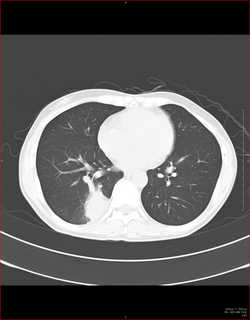

CTで見ると…

3Dだと、こうなります。

気管狭窄ですね。こういう所見もレントゲンで捉えることができるのです。